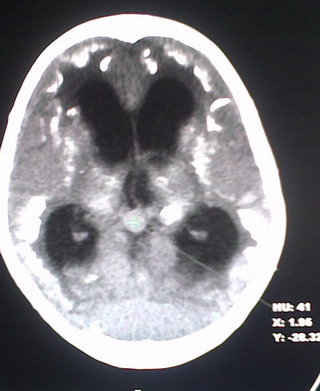

以下是引用jiajie在2009-2-3 20:02:00的发言:[br]脑室周围白质区可见大量斑片状钙化,部分融合成带状,双侧侧脑室及第三脑室扩大。[br]考虑弓形体原虫感染。(先天性宫内感染、torch综合症)

以下是引用lkc8963在2009-2-3 21:15:00的发言:[br]临床眼睑可见静脉扩张,ct双侧眼上静脉亦示扩张,颅内钙化以皮层\\软脑膜为主而不是位于白质和室管膜,再加上静脉窦异常,还是应该考虑静脉血管瘤病,可能为较复杂的血管畸形.

以下是引用卜一在2009-2-4 9:21:00的发言:[br]sturge-weber综合征:面部三叉神经分布区的毛细血管性或海绵状血管瘤以及同侧枕、顶或额叶软脑膜的血管瘤(以静脉性为主)。脑皮质,特别是第二三层,毛细血管可有增厚和钙化。局部发生层状坏死、神经细胞脱失、萎缩、胶质细胞增生及钙盐沉着。可根据面部典型分布的特征性皮痣作出诊断。头颅ct:发现面部血管瘤同侧的脑内病理钙化影,呈双层线条波浪形、脑回形或树枝形。本例支持:sturge-weber综合征![br]